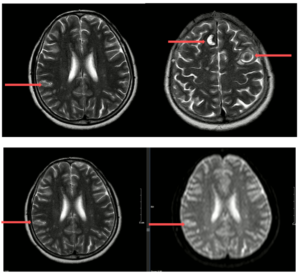

Điều trị bệnh nhân ung thư phổi giai đoạn muộn có di chứng liệt 2 chi dưới tại Bệnh viện Bạch Mai GS.TS.Mai Trọng Khoa, PGS.TS. Phạm Cẩm Phương, ThS.BS.Lê Văn Long, BS. Nguyễn Đăng Khôi Trung tâm Y học hạt nhân và Ung bướu Bệnh viện Bạch Mai Tại...